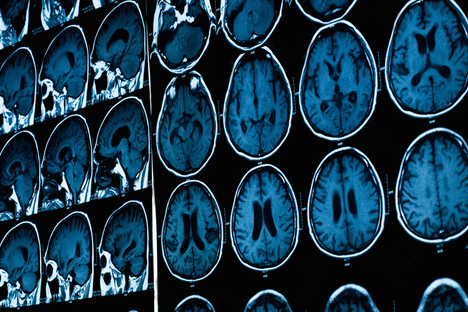

Researchers at Indiana University are conducting a study to determine exactly how marijuana affects the structure and function of the brain. Magnetic resonance imaging (MRI) is being employed to analyze 90 participants, all ages 18 to 35, comprised of current and former pot users, as well as those who have never used marijuana.

Participants will be asked to undergo tests of perception, memory and thinking, and report any issues they may be experiencing as a result of their pot use. The research team will then conduct connectivity analysis on the data culled from all three groups to determine the efficiency of communication between the brain regions. “I like to think of the brain as an electrical circuit,” said study co-leader Sharlene Newman, an associate professor at Indiana University and head of the school’s Brain Imaging Facility.

“If the insulation on the wires is not intact, you can get current leakage resulting in faulty communication,” Newman added. “If the connections between brain regions are faulty, then the functioning of the brain will be faulty or inconsistent. With the MRI techniques we will use, we will be able to examine the integrity of the insulation.”

Newman and study co-lead Brian O’Donnell have authored previous studies that have concluded that cannabis alters connectivity in the brain, making it operate in a less efficient manner. The new study hopes to determine whether brain function recovers after individuals stop using the drug for an extended period of time.